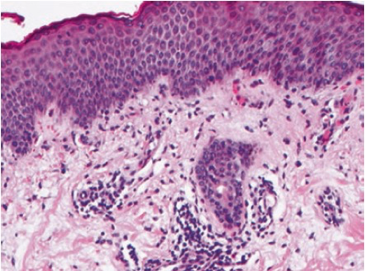

Les lésions histologiques des colites aiguës actives associent un infiltrat inflammatoire polymorphe du chorion, des ulcérations/érosions du revêtement de surface, des exocytoses à polynucléaires neutrophiles responsables de lésions d’abcès cryptiques et éventuellement des granulomes épithélioïdes 2. En immunomarquage, l’infiltrat immun est majoritairement constitué de cellules CD8+ et de Treg+ (sous anti-PD-1/PDL-1) et de CD4+ (sous anti-CTLA-4).

En cas de colites microscopiques lymphocytaires, l’infiltration lymphocytaire intra-épithéliale touche le revêtement de surface mais aussi les cryptes 3, 5.

[Figure 2]

Histologies de colites aiguës actives